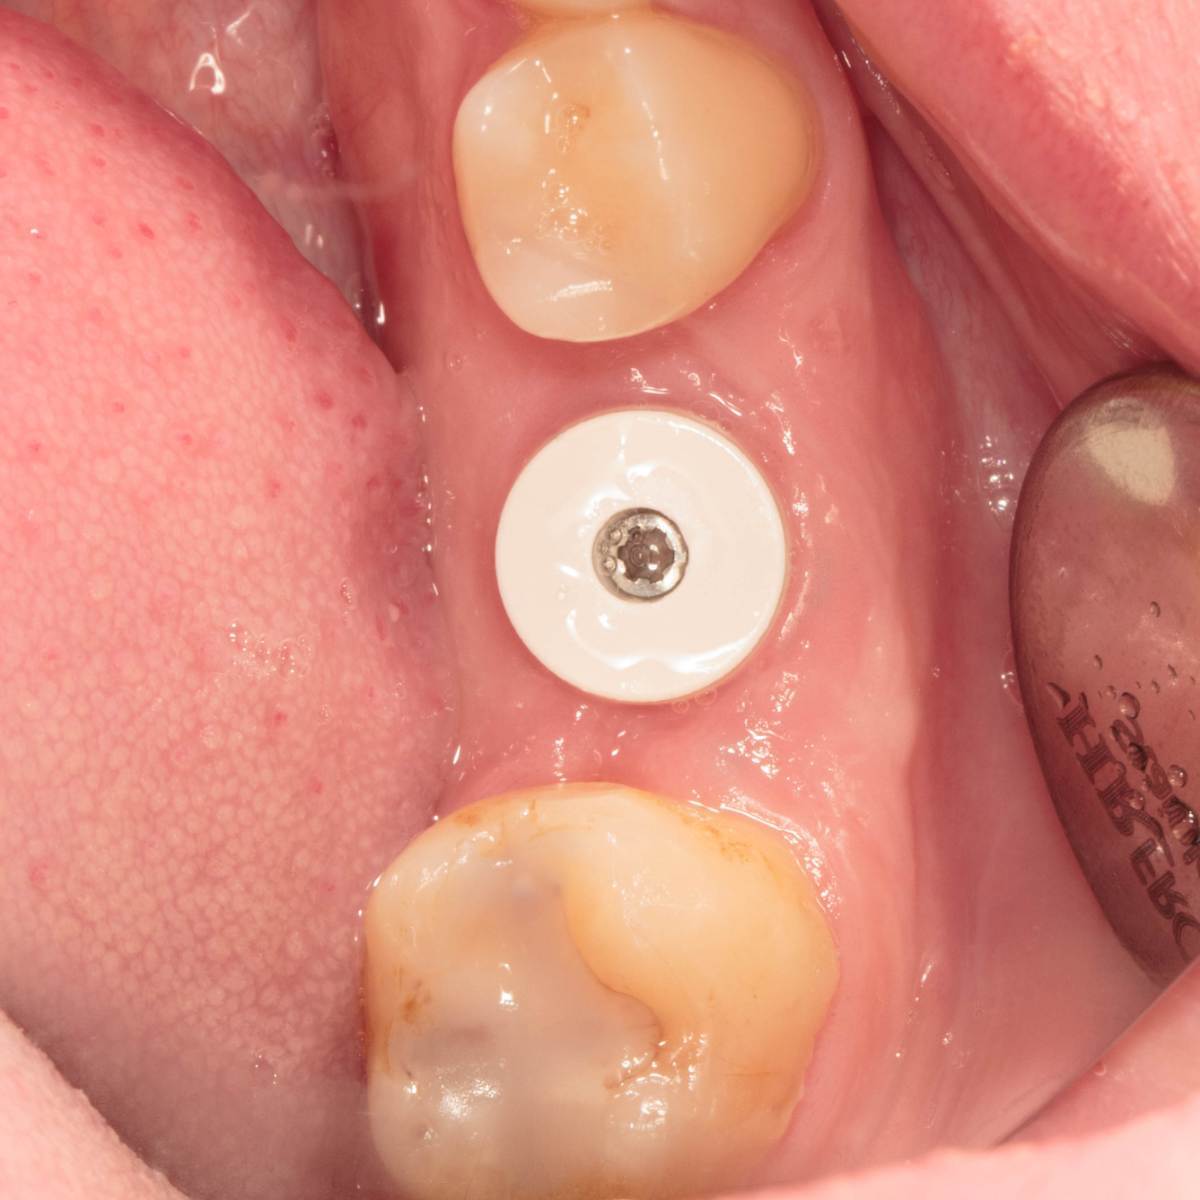

Doctor Vlad Опубликовано 1 марта, 2025 Поделиться Опубликовано 1 марта, 2025 Красиво! А часто косточка в таких лунках требуется? И как часто она там кашей лежит? Не обращали внимание? Здесь перегородка мощная, имплант скорее в аутокости находится. А вот когда не полностью и неудача с аугментатом. Сверху губка изолирует от полости рта? И что это за белый формирователь? Ссылка на комментарий

Женька Опубликовано 2 марта, 2025 Автор Поделиться Опубликовано 2 марта, 2025 @Doctor Vlad Спасибо! Ну, то что на фотках это же только было-стало) а по факту, первая позиция, она же на фото, была не верная, пересверливался и разбил перегородку. Но торк, тем не менее, получил) Губку не изолировал. Белый формик - это родное решение у Неодент. Формики 5.5 и 7.0 только из PEEK. И мне они нравятся меньше, чем титановые у корейцев, например. @Estes ССТ же подшивал, всё в тексте. Ссылка на комментарий

Женька Опубликовано 8 апреля, 2025 Автор Поделиться Опубликовано 8 апреля, 2025 3 месяца спустя 2 1 1 Ссылка на комментарий